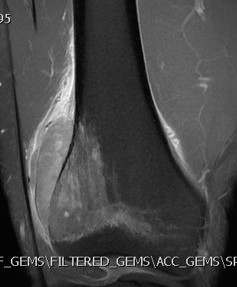

MRI

Low signal intensity of T1 / high signal intensity on T2

- intramedullary extent

- skip lesions

Significant soft tissue mass with significant edema

Ewing's distal femur